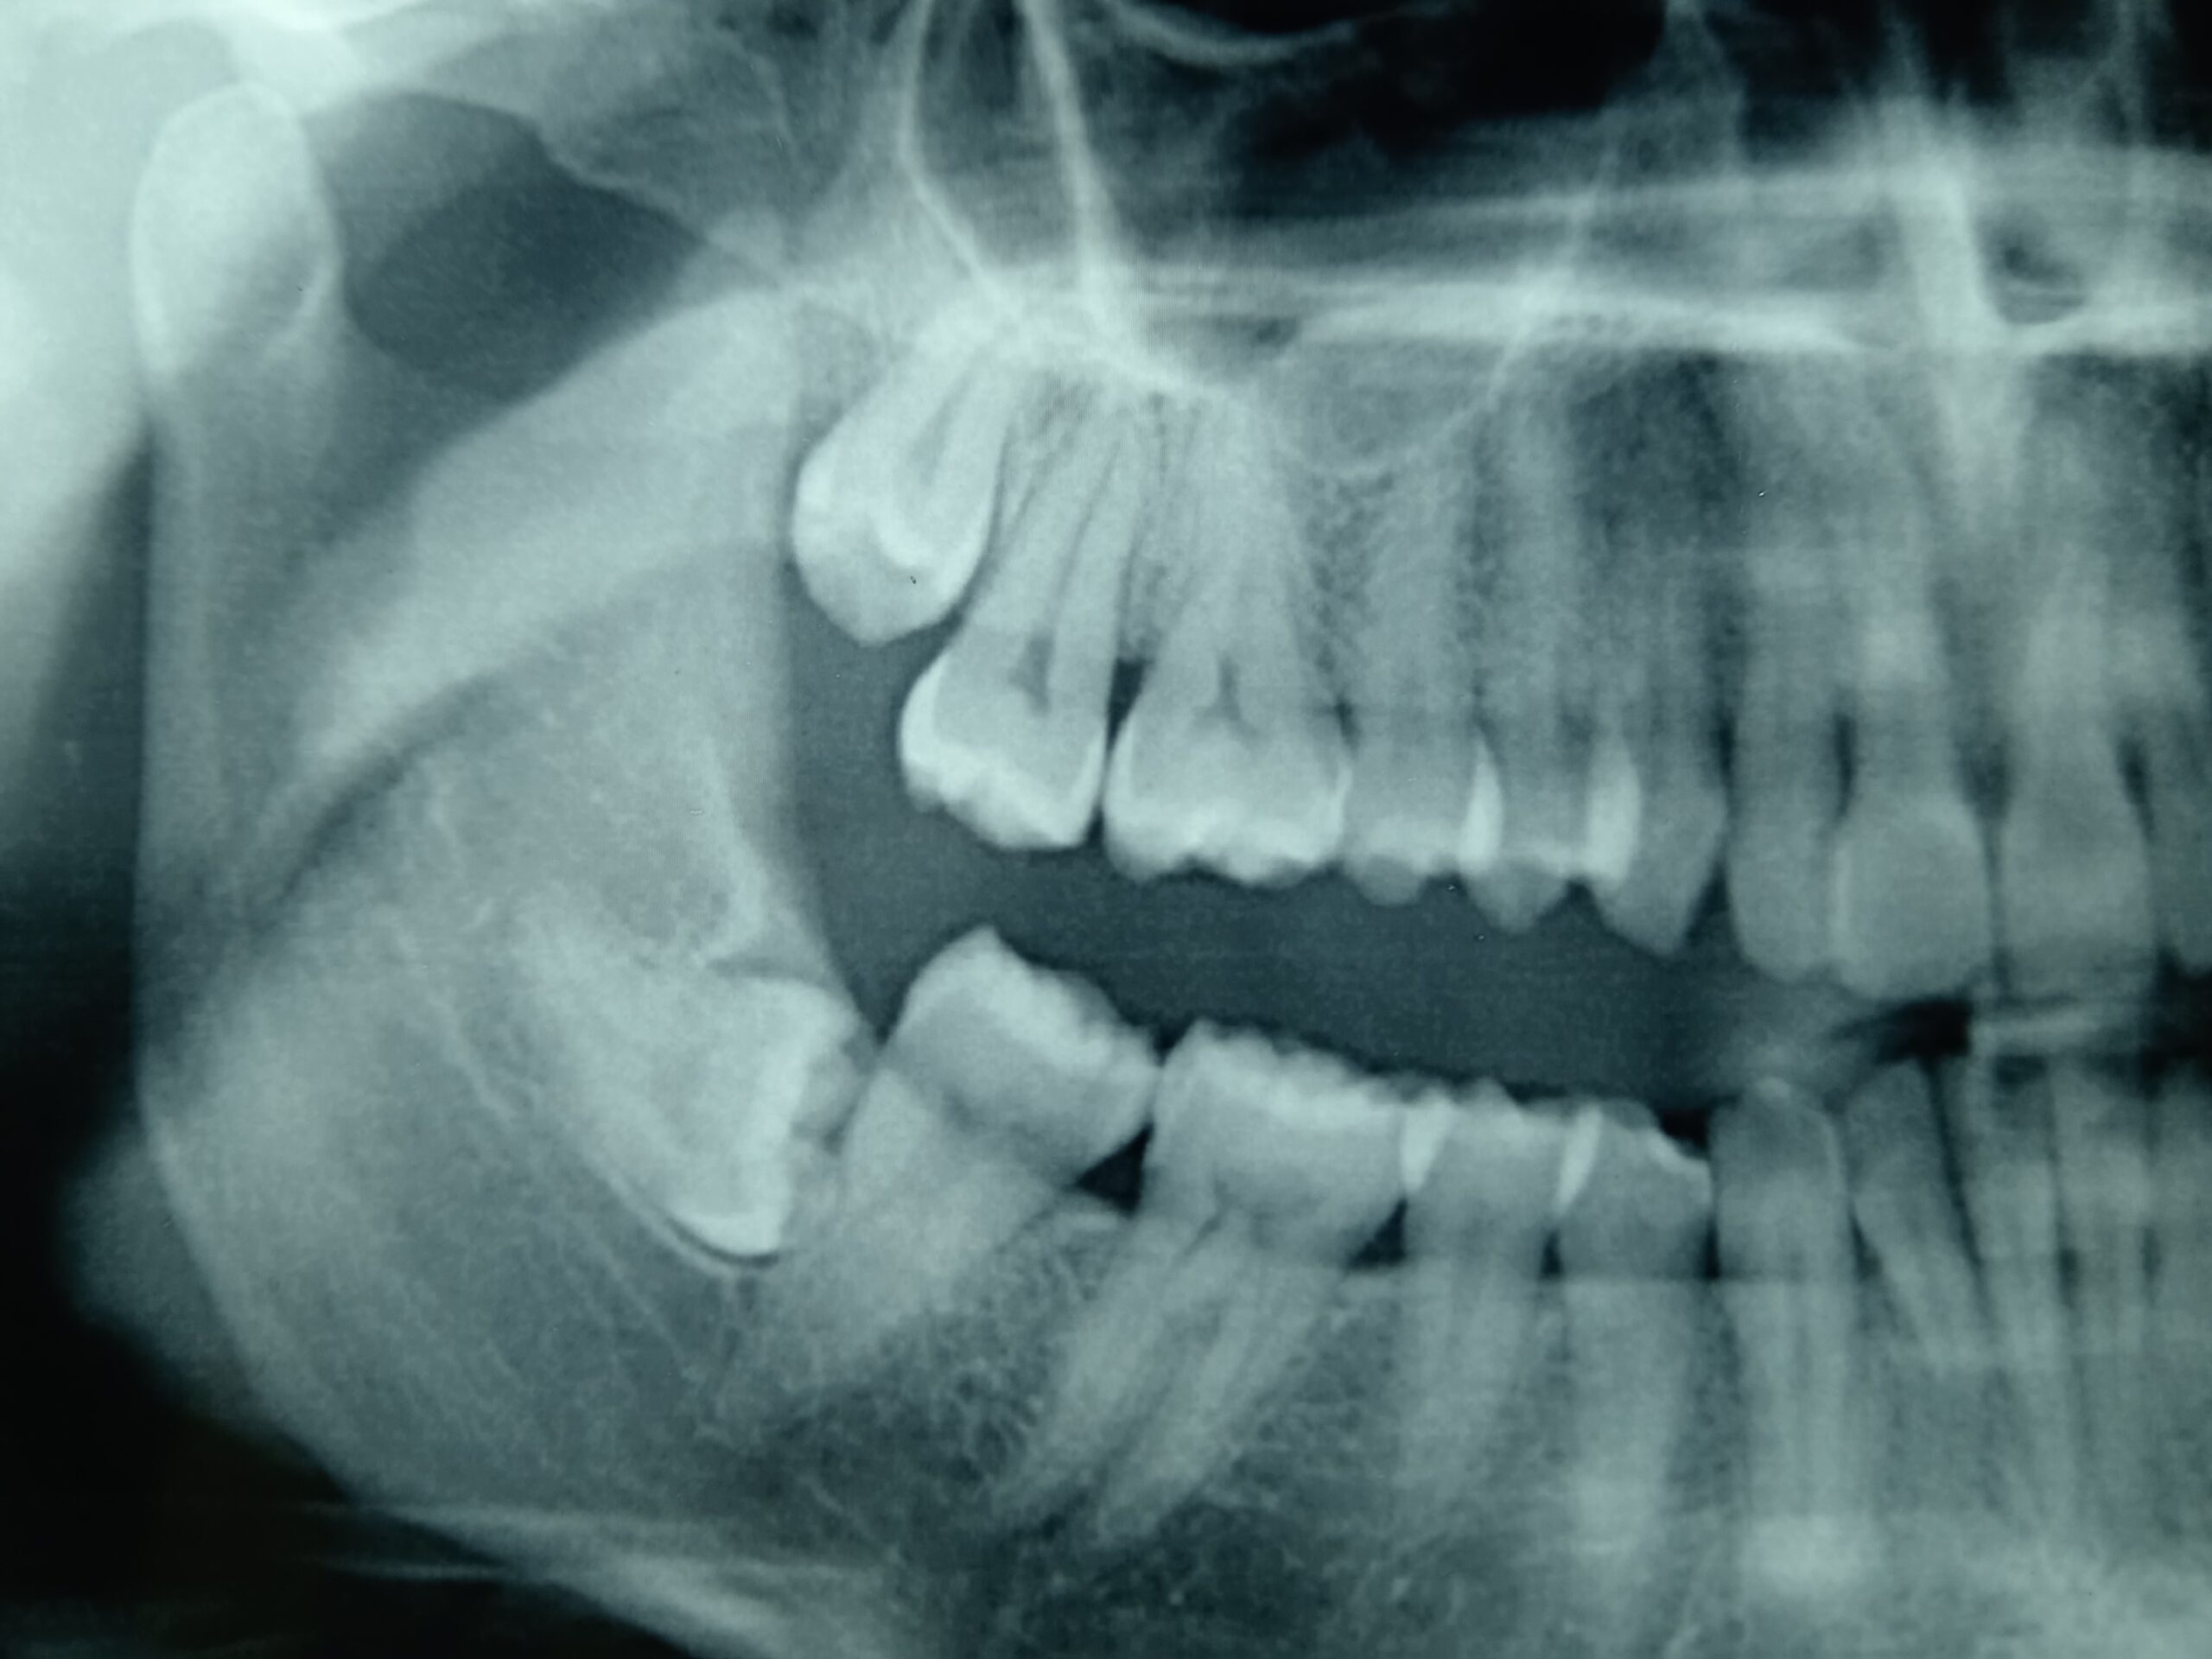

Usiamo strumenti diagnostici avanzati come esami radiografici di ortopantomografia (OPG) e Tac DentalScan per una valutazione completa della situazione dentale.

In caso di mal posizionamento o sintomi, l’estrazione è spesso la soluzione migliore. Si praticano incisioni per esporre il dente, con la possibilità di separalo in parti per facilitarne la rimozione.

Se le radici del dente sono in contatto con il nervo mandibolare, questo intervento rimuove solo la corona del dente, lasciando le radici intatte per evitare di causare danni al nervo.